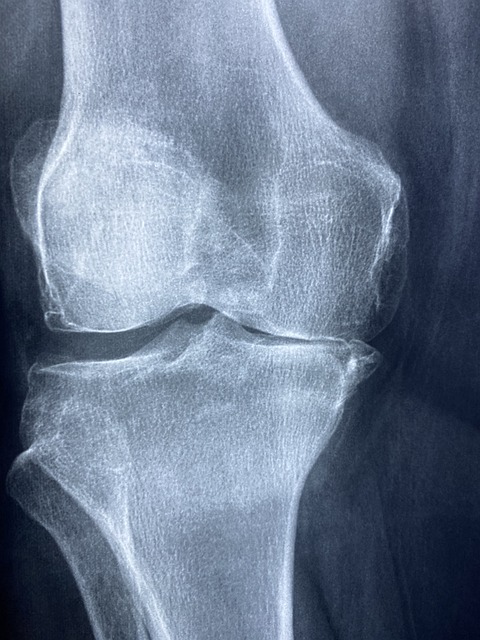

무릎 인공 관절 수술은 무릎 관절의 연골이 닳아 뼈와 뼈사이가 맞닿아 일어나는 통증을 일으키는 퇴행성 관절염을 위한 수술입니다. 무릎의 연골은 노화 또는 과사용 그리고 알 수 없는 이유로 인한 빠른 노화로도 발생할 수 있습니다. 여성분들에게 많이 나타나며 무릎 인공 관절 수술 전문의들은 앞으로 여성의 80%가 무릎 관절 수술을 하게 될 거라 예측하고 있습니다.

무릎 인공 관절 수술은 세계적으로도 성공적인 수술 방법으로 인정받는 만큼 수술 후 90%의 통증 감소, 15년 후에도 85%의 높은 만족도를 보인다고 합니다.

무릎 인공 관절 수술을 고민하시는 분들의 가장 큰 고민은 수술 시기와 병원 선택 일 텐데요. 전문 의사들은 관절의 수명을 길게 15~20년으로 보기 때문에 70세 이상에 하는 걸 권하고 있습니다. 하지만 퇴행성 관절염 4기에 비수술 치료로도 효과가 없고 극심한 통증을 갖고 있다면 60대에도 수술을 하는 것이 좋다고 합니다. 극심한 통증의 4기 시기이면 어차피 비수술의 치료로는 효과를 보기가 어렵다고 합니다.